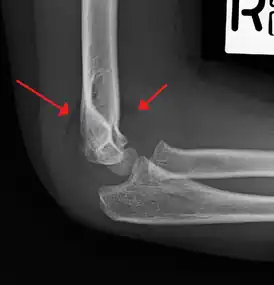

| An elbow X-ray showing a displaced supracondylar fracture in a young child | |

A supracondylar humerus fracture is a fracture of the distal humerus just above the elbow joint. The fracture is usually transverse or oblique and above the medial and lateral condyles and epicondyles. This fracture pattern is relatively rare in adults, but is the most common type of elbow fracture in children.[1] In children, many of these fractures are non-displaced and can be treated with casting. Some are angulated or displaced and are best treated with surgery. In children, most of these fractures can be treated effectively with expectation for full recovery.[2] Some of these injuries can be complicated by poor healing or by associated blood vessel or nerve injuries with serious complications.